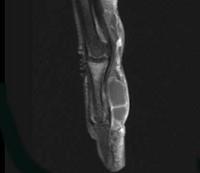

问题 女,77岁,发现右手部肿块二周,请结合影像图像提出最可能的诊断 ( )

选项 A、血管瘤 B、以上都不是 C、多发性腱鞘囊肿 D、骨囊肿 E、肌内脓肿

答案 C